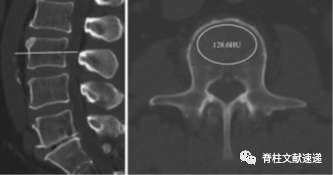

应用CT豪斯(HU)预测螺钉松动

CT除了在诊断螺钉松动方面有价值,在预测螺钉松动方面也有意义。目前相关的基于CT豪斯单位的螺钉松动预测也有多篇重要文章发表。

(CT豪斯单位的测定,可以从影像科获得相关数据)

本文是北医三院的教授们关于CT的豪斯单位在预测螺钉松动方面的研究,作者回顾性纳入了503例患者,其总的螺钉松动率为30%,松动组的既往CT豪斯单位明显低于未松动组,据此作者认为CT豪斯单位可以作为椎弓根螺钉松动的独立预测因素,而CT豪斯单位较低与螺钉松动的存在明显负相关,即CT豪斯单位越低,发生螺钉松动风险越高。

同样是该院同一作者的另一篇文章认为CT豪斯单位预测螺钉松动的价值甚至高于骨密度测定。